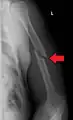

A spiral fracture of the distal one-third of the humerus shaft